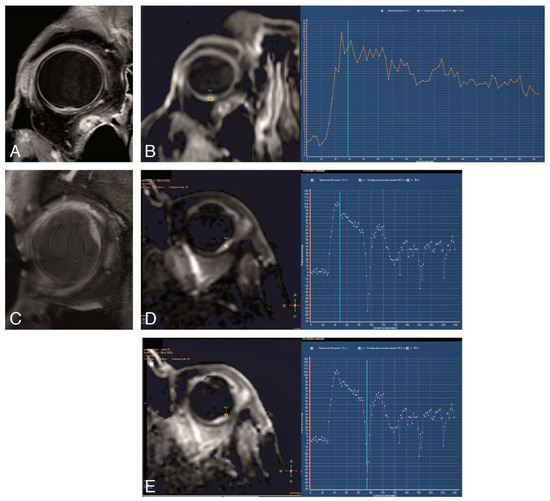

4.3. Functional MRI of Uveal Melanoma